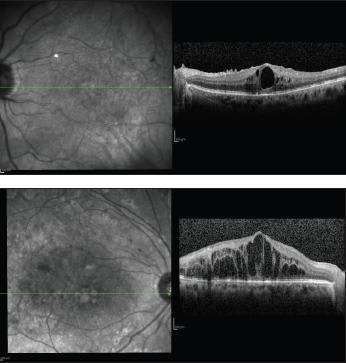

Macular traction is a well-known factor in the development of CME. Previous investigators have reported on the anatomical improvement and visual benefit of pars plana vit rectomy in persistent DME.24-31 In addition, improvement of BCVA and significant reduction of macular thickness were documented following vitrectomy for diffused DME combined with vitreomacular traction.27,28 Recchia et al. suggested that pars plana vitrectomy with ILM peeling may provide anatomical and visual benefit in DME.26 In contrast, another researcher found that vitrectomy and ILM peeling for refractory DME in the absence of vitreomacular traction failed to improve visual acuity.32-34 Thus, pars plana vitrectomy with ILM peeling should be reserved for selected cases (Figure 5).

Figure 5. A patient with severe cystoid macular edema with epiretinal membrane before (left) and after (right) vitrectomy with internal limiting membrane peeling. Vision improved from 20/50 to 20/32. Note the integrity of the outer retinal layer, external limiting membrane, photoreceptor inner segment, outer segments and retinal pigment epithelium.